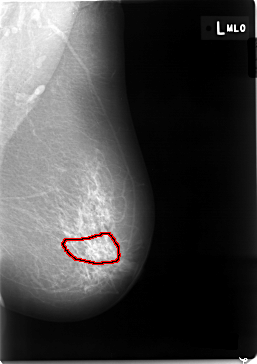

C_0002_1.LEFT_MLO

LEFT_MLO LINES 5824 PIXELS_PER_LINE 4104 BITS_PER_PIXEL 12 RESOLUTION 50 OVERLAY

FILE: C_0002_1.LEFT_MLO.OVERLAY

TOTAL_ABNORMALITIES 1

ABNORMALITY 1

LESION_TYPE CALCIFICATION TYPE PLEOMORPHIC DISTRIBUTION SEGMENTAL

ASSESSMENT 4

SUBTLETY 1

PATHOLOGY MALIGNANT

TOTAL_OUTLINES 1

BOUNDARY